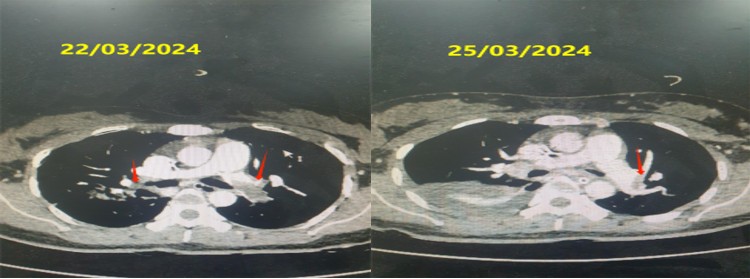

Tại đây, chị S đã ngừng tuần hoàn hô hấp và bác sĩ đã kích hoạt báo động đỏ, triệu hồi kíp cấp cứu và hội chẩn ngay tại Bệnh viện. Sau 10 phút cấp cứu, tim chị S đã đập trở lại và chị được chuyển lên khoa Hồi Sức Ngoại để tiếp tục điều trị. Sau khi thăm khám và các xét nghiệm, bác sĩ nghi ngờ chị S bị thuyên tắc phổi cấp và đã tiến hành các biện pháp chẩn đoán và điều trị ngay. Chị S được sử dụng thuốc tiêu sợi huyết r-TPA và heparin để tan huyết khối trong động mạch phổi.

Dần dần, tình trạng của chị S đã ổn định hơn và sau 19 ngày điều trị, chị đã được xuất viện. Mặc dù không giữ được thai nhi, nhưng bác sĩ Bệnh viện Quân y 103 đã cứu sống thành công chị S. Đây là một trường hợp rất nặng, nhưng nhờ sự phối hợp chặt chẽ giữa các chuyên khoa và phương án điều trị kịp thời, chị S đã hồi phục và trở lại cuộc sống bình thường.